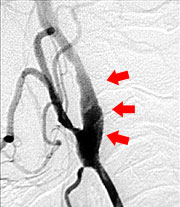

さて当科では脳梗塞予防手術を積極的に行っています。最近食生活の欧米化で内頚動脈起始部狭窄症が増加しています。この病気に対しては外科的治療と血管内治療がありますが、当科では主に外科的治療によって内頚動脈の厚くなった内膜を剥離して血管を広げ、脳梗塞を予防しています(図9、10)。